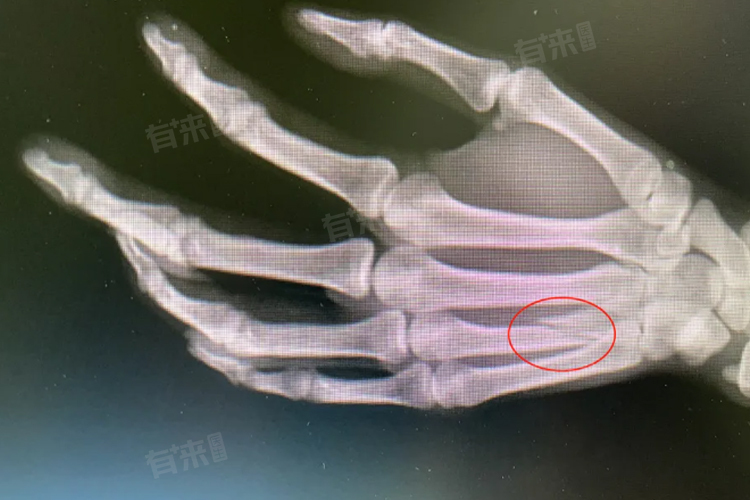

- 复杂骨折恢复时间长,如粉碎性、涉及关节面或有明显移位的骨折,处理难度大,复位固定要求高,周围组织损伤严重,通常需6-8周甚至更久达临床愈合,且要防并发症。

- 复位环节是治疗的关键步骤,医生会根据骨折的具体情况选择合适的复位方法。如果骨折相对简单,可能会采用手法复位,在麻醉状态下,通过专业的手法操作将骨折断端恢复到正常位置。而对于复杂骨折,则需要进行手术复位,在直视下精确地对骨折部位进行处理,以确保良好的对位对线。

- 外固定如石膏或夹板常用于稳定骨折部位,为骨折愈合提供稳定的环境。石膏固定塑形好,适用于多种骨折;夹板固定则可根据肿胀调整。内固定在手术复位后进行,使用钢板、螺钉等器械进一步固定骨折断端,增强稳定性。